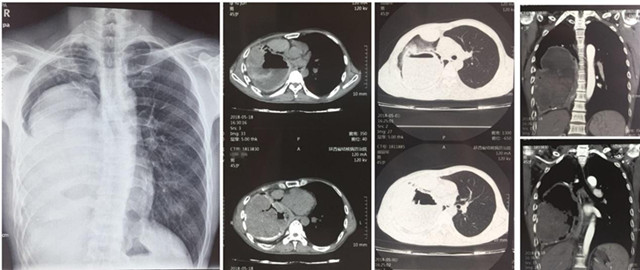

来自渭南澄县的45岁黄某患上了一种奇怪的病,10年前,他无明显诱因出现咳血伴有头晕和乏力,当时由于咳血量小,加之家庭经济条件差并未重视,只要出现该症状都自行购买药物治疗,近5年来咳血频次明显增加,每次咳血量达100ml以上,家人带着他辗转咸阳、西安多家医院,均考虑为肺结核伴脓胸,给予抗痨治疗,但无法有效控制反复出现的咳血症状,眼看黄某身体状况每况愈下,家人心急如焚。5月15日,家人携患者抱着最后一线希望来到陕西省结核病防治院外科,接诊的陈其亮主任医师和李军孝副主任医师对他进行了详细快速的检查,发现患者血压只有90/60mmHg,血色素75g,医生紧急给患者纠正贫血预防休克治疗后,进一步检查发现患者右侧胸腔内可见一罕见的巨大包块,占据80%的胸腔,包块内密度不均匀,右上胸腔仅有的肺组织也呈蜂窝病变结构。让人不解的是,患者既然被我省多家医院诊断为“结核性脓胸”,但从我院诊查后来看,无论是影像形态、生化检查,还是病原病检均无结核感染依据;而且伴随长期咳血的源头是否和占位灶及其滋养血管有关不得而知。目前治疗的唯一手段就是手术,但盲目手术,则是雪上加霜,死亡风险极大。陈其亮科主任及李军孝副主任在科内对患者病情进行详细的讨论和分析后,考虑患者最大的可能是肺源性支气管囊肿并混合感染。由于胸内占位病灶滋养血管丰富,走形错综复杂,压力较大,若不及时控制,患者随时有大咳血至休克死亡的可能。时逢我院承办首届“一带一路”结核病长安论坛之际,陈其亮主任特邀参会嘉宾复旦大学公卫中心胸外科宋言峥主任、山东胸科医院胸外科金锋与影像科候代伦主任为患者会诊,经过论证认为我院外科的针对该病的手术方案(胸膜全肺切除术)指征明确,具有可实施性。

经过精心而充分的准备,陈其亮主任、李军孝科副主任、崔渊博主治医师和麻醉科王君毅医师等按照拟定的手术方案,于5月28日晨8时准时时开始,术中果然出现术前所预料的胸腔创面渗血,肺门粘连及血管畸变等问题,随着手术的推进,患者血压持续偏低(90-60/50-30mmHg),但这些都被我们术前制定的术中紧急应对预案一一化解,经过约4小时50分钟顺利完成胸膜全肺切除,术中共输血3200ml,术后生命体征平稳,术后病理回报印证了术前的诊断。截止目前患者恢复良好,再未出现咳血等呼吸道不适症状,血色素已恢复正常,患者转危为安,家人激动的说:“这么多年的病搞清了,也治愈了”。